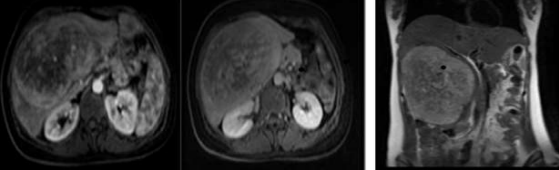

A 41-year-old woman was referred to our clinic with complaints of fever, good performance (Eastern Cooperative Oncology Group 1), no weight loss, no comorbidities, and no surgical history. Upon examination, there was a firm-to-hard, non-tender liver mass extending 13 cm below the right costal margin with rounded borders. All laboratory investigations, including liver function tests, viral markers, and tumour markers, were normal (alpha-fetoprotein< 1.3ng/mL). Abdominal multidetector computed tomography (Figure 1) revealed a normal liver size. The liver contours were smooth and the parenchymal density was normal. The hepatic vein, portal vein, and main branches were normal. The intrahepatic bile ducts were normal. A mass lesion, measuring approximately 15x11 cm, is observed near the level of liver segments V-VI-IVB, almost filling the space (HCC-fibrolamellar HCC?) No lymph nodes of abnormal size were observed in the abdomen. No significant free fluid is detected in the abdomen,The chest computed tomography findings were normal, the abdominal Magnetic resonance imaging  (MRI)(Figure 1) showed at the level of segments IVB-V-VI, there is a heterogeneously hyperintense lesion measuring 16.5x14.8x10.2 cm on T2-weighted images, The lesion shows peripheral enhancement predominantly in the early post-contrast phase, followed by  washout from the periphery in the delayed phase, with slightly increased enhancement in the centre, suggesting a possibility of fibrolamellar hepatocellular carcinoma (FH-HCC). The main portal vein and right portal vein branches were compressed by the identified lesion. A Positron Emission Tomography (PET) scan was performed, which revealed a hypermetabolic mass lesion in the liver, with no other lesions identified on the PET scan as the primary site (Figure 2). The primary diagnosis was fibrolamellar hepatocellular carcinoma (FL-HCC).

Figure 1a,  Figure 1b, Figure 1c

Figure1: abdomen (MRI), Figure 1a:(arterial phase) showing an enhancing lesion, Figure 1b:(delayed phase) showing slight washout, Figure 1c:(coronal T2 weighted) showed a heterogeneous mass in the right liver lobe.